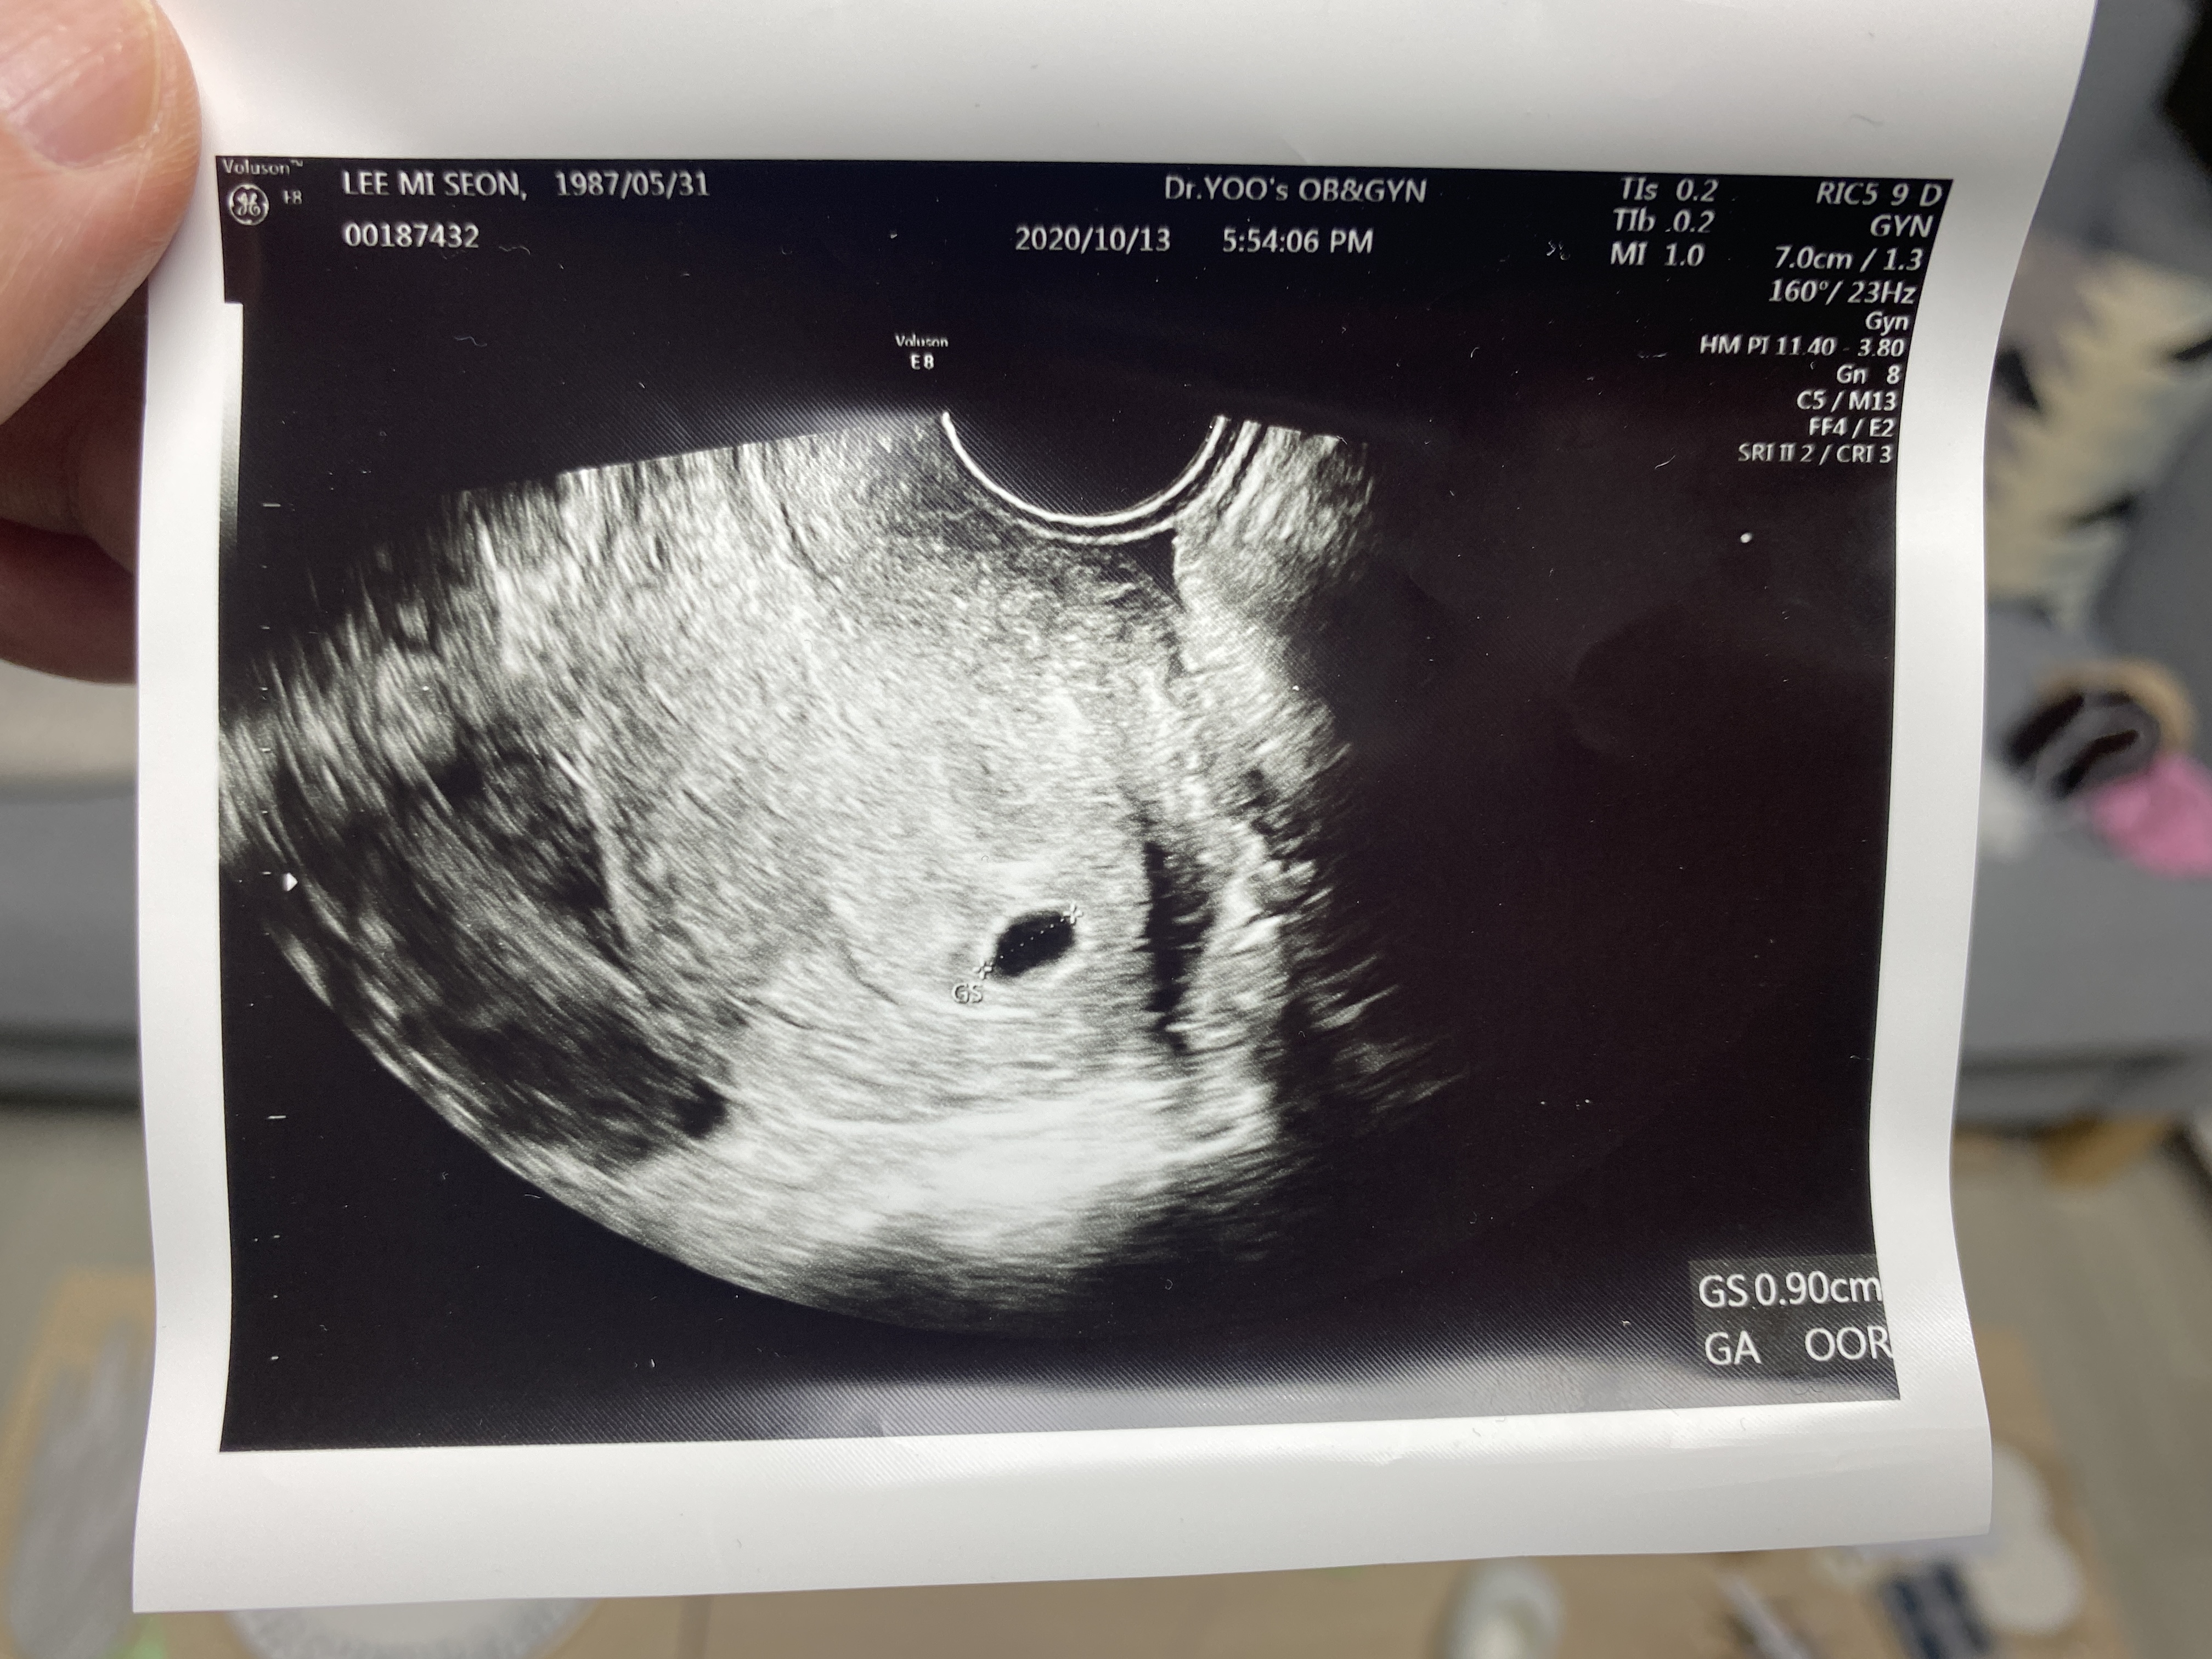

오늘은 5주2일째, 아기집을 볼 수 있는 날이라 오후 반차를 내고 와이프와 병원에 다녀왔다

그리고 오늘 초음파로 와이프 뱃속에 떡! 하니 만들어 놓은 아기집을 확인하고는

와이프와 나는 어떻게 말도 못 할 안도의 한숨을 내쉰 듯하다

아기집 크기는 0.9mm 크기로 주수에 비해서 0.3mm는 더 크다고 하시는데